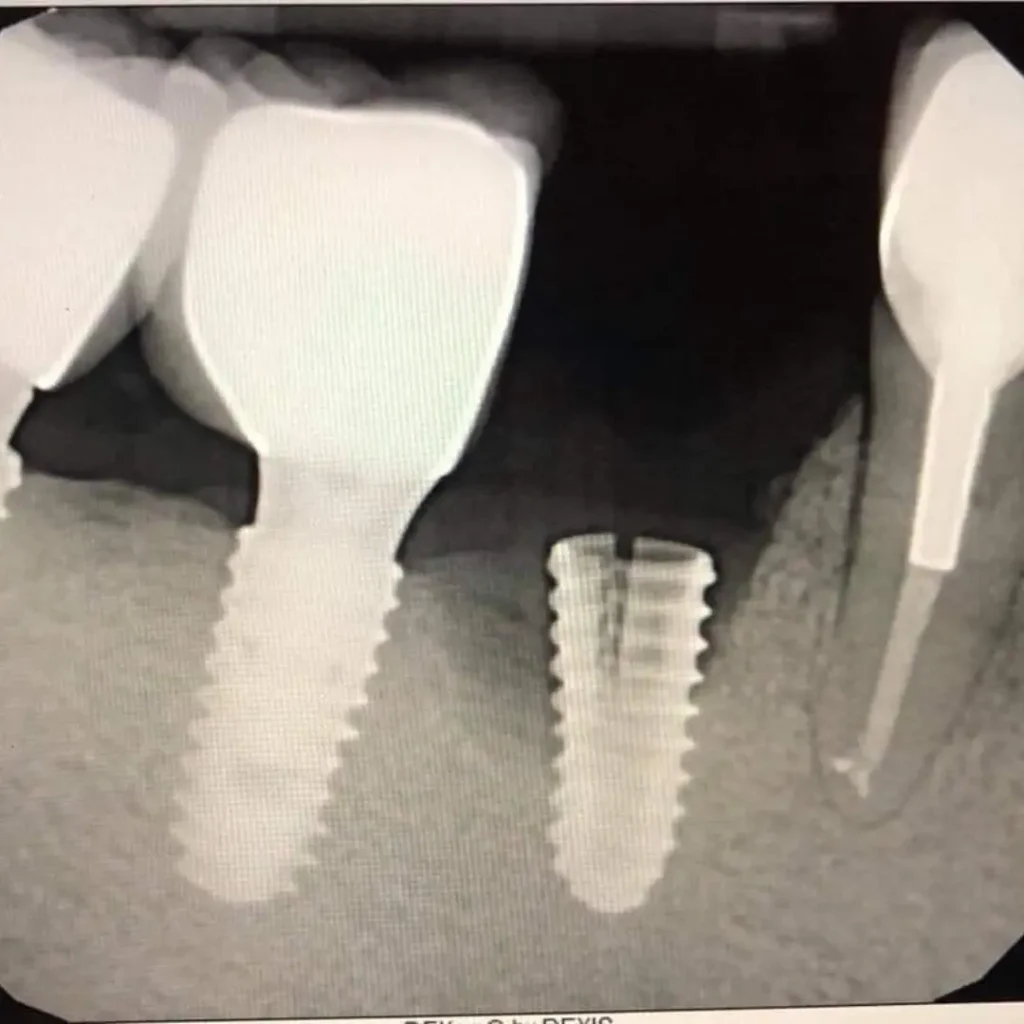

A dental implant emergency includes a loose dental implant, pain or swelling around the implant, a broken crown, or sudden implant failure due to trauma or infection. If left untreated, these issues may affect surrounding soft tissue, bone, or even your overall health, so prompt emergency dental care is crucial.

In cases where there’s bone loss, a bone graft may be required to rebuild the area before the dental implant procedure. Our specialists will evaluate your condition and develop a personalized treatment plan.

Yes. Depending on the issue, we may repair the implant restoration, replace the artificial tooth root, or adjust the surrounding crown or abutment. Our emergency dental services ensure quick, effective care to restore your implant.

Yes, in some emergency cases, we can place an implant immediately after extraction, provided the bone and soft tissue conditions are favorable. This is called immediate placement and reduces the number of visits.